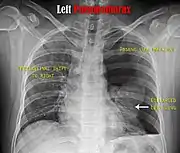

Chest X-ray

A plain chest radiograph, ideally with the X-ray beams being projected from the back (posteroanterior, or "PA"), and during maximal inspiration (holding one's breath), is the most appropriate first investigation.[30] It is not believed that routinely taking images during expiration would confer any benefit.[31] Still, they may be useful in the detection of a pneumothorax when clinical suspicion is high but yet an inspiratory radiograph appears normal.[32] Also, if the PA X-ray does not show a pneumothorax but there is a strong suspicion of one, lateral X-rays (with beams projecting from the side) may be performed, but this is not routine practice.[15][19]

Chest X-ray showing a pneumothorax on the right (left in the image), where the absence of lung markings indicates that there is free air inside the chest

Chest X-ray showing the features of pneumothorax on the left side of the person (right in image)

It is not unusual for the mediastinum (the structure between the lungs that contains the heart, great blood vessels, and large airways) to be shifted away from the affected lung due to the pressure differences. This is not equivalent to a tension pneumothorax, which is determined mainly by the constellation of symptoms, hypoxia, and shock.[13]

The size of the pneumothorax (i.e. the volume of air in the pleural space) can be determined with a reasonable degree of accuracy by measuring the distance between the chest wall and the lung. This is relevant to treatment, as smaller pneumothoraces may be managed differently. An air rim of 2 cm means that the pneumothorax occupies about 50% of the hemithorax.[15] British professional guidelines have traditionally stated that the measurement should be performed at the level of the hilum (where blood vessels and airways enter the lung) with 2 cm as the cutoff,[15] while American guidelines state that the measurement should be done at the apex (top) of the lung with 3 cm differentiating between a "small" and a "large" pneumothorax.[33] The latter method may overestimate the size of a pneumothorax if it is located mainly at the apex, which is a common occurrence.[15] The various methods correlate poorly but are the best easily available ways of estimating pneumothorax size.[15][19] CT scanning (see below) can provide a more accurate determination of the size of the pneumothorax, but its routine use in this setting is not recommended.[33]

Not all pneumothoraces are uniform; some only form a pocket of air in a particular place in the chest.[15] Small amounts of fluid may be noted on the chest X-ray (hydropneumothorax); this may be blood (hemopneumothorax).[13] In some cases, the only significant abnormality may be the "deep sulcus sign", in which the normally small space between the chest wall and the diaphragm appears enlarged due to the abnormal presence of fluid.[16]